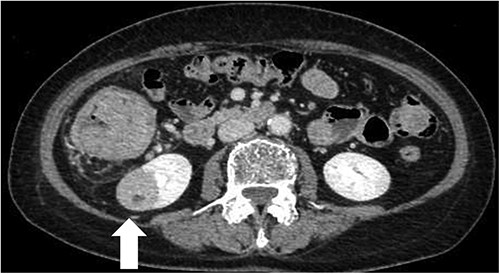

After switching to the medial approach, the ileocolic vessels and the right branch of the middle colic vessels were dissected and secured using a Hem-o-lok® clip. The hepatic flexure was removed from the lateral and cranial sides, and the right hemicolon was completely mobilized from the Toldt fascia. After undocking, the trocar sites were temporarily closed. The patient was then placed in the left flank position. Reusing the port site on the right lower abdomen, three additional 8 mm trocars and one 12 mm trocar for assistance were inserted (Fig. 4). The robot was then redocked to the patient’s right side. Partial nephrectomy was performed by urologists using the arterial clamp technique. The kidney specimens were then placed in an endobag. The robot was undocked, and the trocar sites were completely closed. The warm ischemic time was 15 min. The patient was placed in the supine position again. The gastroenterologists resumed the surgery. The umbilical incision was extended up to 4 cm and protected by a wound retractor®. The kidney specimen and right hemicolon were removed, and lymph node dissection was performed. The bowel was transected with a 60-mm linear stapler, Echelon®, and a functional end-to-end anastomosis was performed. A suction drain was laparoscopically placed under the liver. During the surgery, three postural changes and two dockings were required. The total operative time was 328 min: 140 min for right hemicolectomy without bowel resection, 118 min for partial nephrectomy and 70 min for bowel resection, anastomosis and fascia closure. The estimated blood loss was 30 ml. The colon with ligated vessels was intraperitoneally for ~2 h, but lactate was within normal range after the operation. The patient’s postoperative course was uneventful. The patient resumed eating on postoperative Day 3. The drain was removed on postoperative Day 6. The patient was discharged on postoperative Day 11. The pathological diagnoses were papillary adenocarcinoma of the ascending colon, stage pT3N0M0, and chromophobe renal cell carcinoma of the right kidney, stage pT1aN0M0. The patient remained cancer-free with no evidence of recurrence 6 months after surgery.

Trocar placement for robotic right partial nephrectomy with the patient in the left flank position. R1, located in right lower abdomen, was shared with the gastroenterologists.